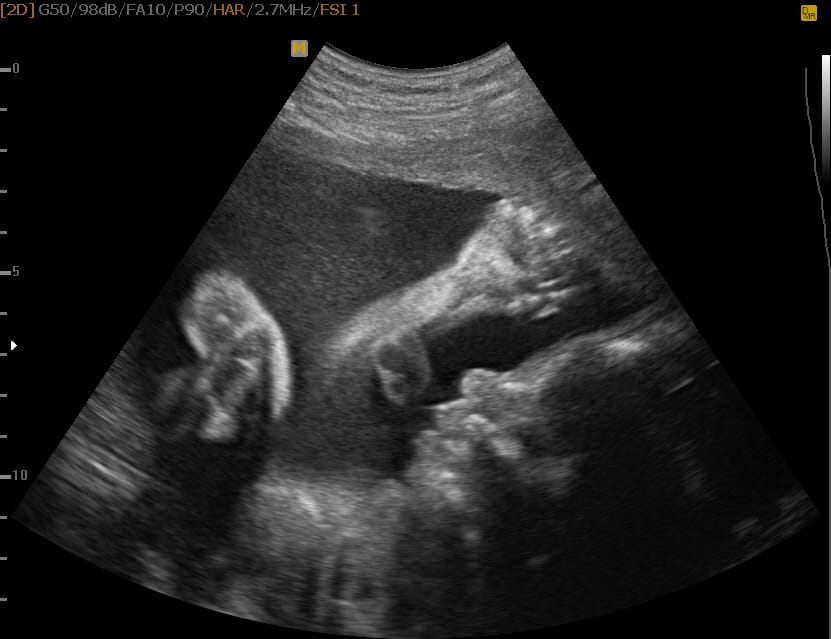

To je najin sin v 3D/ 4D tehniki

Že res, da bo najin sin čez približno tri mesece prijokal na svet, a zakaj si ga ne bi ogledala že danes? Prvi ultrazvok je bil nepozabno popotovanje. Šlo je za 3D pregled. Ko sva izvedela, da je na voljo tudi pregled v 4D tehniki, se mu nisva mogla upreti.

Za pregled sva se odločila, ker je to edinstvena priložnost, da s pomočjo napredne tehnologije vidiš, kako je videti tvoj otrok, ko je še znotraj mamice.

Glavico sem takoj prepoznal, potem pa se je že zataknilo. Naslednja stvar, ki naj bi jo gledal, je bila srček, ali je bilo to oko, ki mežika? Seveda nisem nič rekel, samo pisano sem gledal v zaslon in kimal. Vse skupaj se je še bolj zakompliciralo, ko je zdravnica vklopila 4D tehniko. Razlagala je, da so to, kar gledamo oči, čeprav sem mislil, da gledam popek. Tudi lulčka nisem videl, kljub temu, da je zdravnica večkrat poudarila, da je fant dobro obdarjen. Seveda sem bil ponosen.